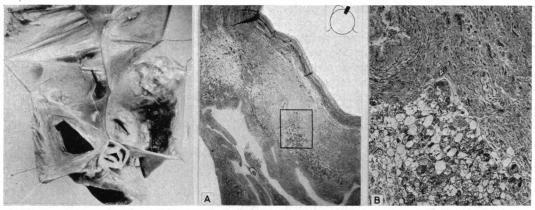

There is a remarkable remnant of primitive fibres persisting at the sino-auricular junction in all mammalian hearts. These fibres are in close connection with the vagus and sympathetic nerves, and have a special arterial supply; in them the dominating rhythm of the heart is believed to normally arise. Keith and Flack, 1907.

在所有哺乳动物的心脏中,原始纤维的显著残余部分持续存在于窦房交界处。这些纤维与迷走神经和交感神经紧密相连,并有特殊的动脉供应;人们认为心脏的主导节律通常起源于此。基思和弗莱克,1907年。